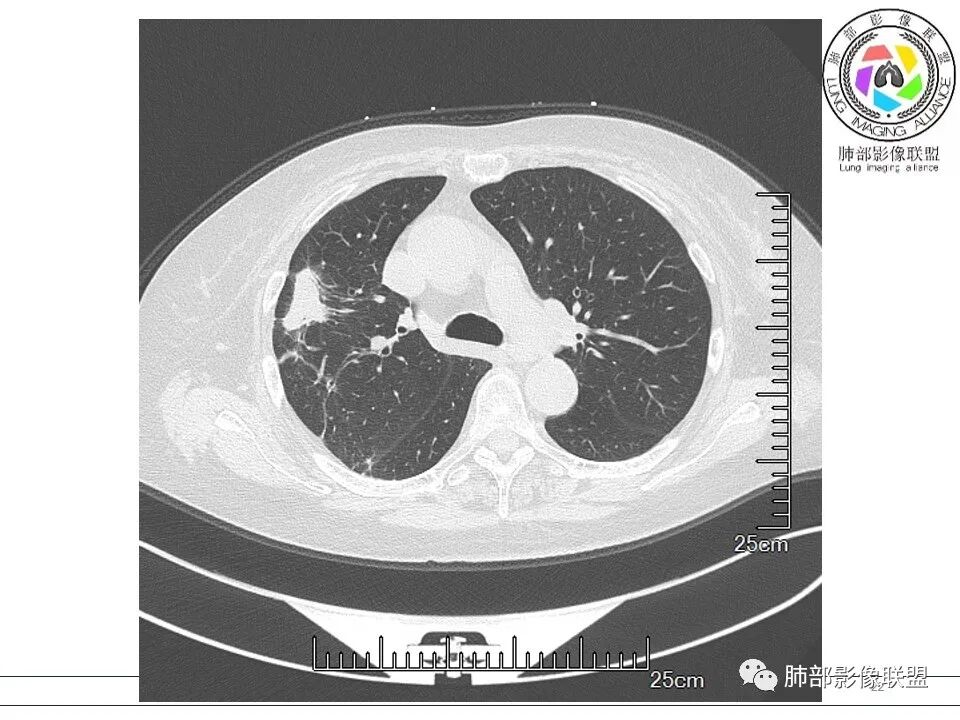

衡妈: 老年女性,右肺上叶沿胸膜下不规则实性病灶,长轴平行于胸膜,有结节融合感,边缘部分彭隆部分平直,周围可见数条纤维灶影,病灶内可见充气支气管征未达远端,首诊考虑慢性炎性肉芽肿,隐球菌?机化性肺炎?建议增强扫描及ct下穿刺活检。

放射线 (王秀仙): 右肺上叶胸膜下结节样影,边缘平直收缩,胸膜牵拉,支气管进入病灶并扩张,部分支气管进入后阻塞,长轴平行于胸膜,周围可见片状及条索状影,隐球?机化性肺炎?

晨读:女,70,未诉症状。风湿性多肌痛病史,口服强的松等药物治疗。胸部CT:右肺上叶多发不规则斑片影,沿支气管分布,部分病灶侧向融合、平行于胸膜,边缘平直内收为主、部分彭隆,周围模糊晕、可见数条纤维灶影,胸膜牵拉,病灶内可见充气支气管征、管腔不畅,考虑慢性炎症,PC?OP?鉴别腺Ca、SCLC等。

南边: 这个病例大方向没问题,炎性。目前大家都是考虑:隐球菌病、OP,其实这两个结论有重叠,而且这个病例很值得讨论,可惜,估计没有证实。影像特点:病灶长轴与胸膜平行,侧向融合特点明显,符合隐球菌病,问题是目前的状态,边缘收缩明显

内部支气管扩张,周围少量GGO,而且病灶离开了胸膜,附近长索条影,支持机化的改变

问题是:需要抗真菌?还是按OP治疗?我个人认为这阶段的改变目前不是病原菌引起的,而是炎性反应后期修复的改变,应该抗OP为主

5、分布:隐球菌肺炎是肺泡性炎症,病灶分布多位于胸膜下,可紧贴胸膜,也可与胸膜邻近,病灶长轴与胸膜平行。(划重点,分布特点非常重要,因为隐球菌如果没有荚膜,会被巨噬细胞吞噬,在人体内是无法生存。隐球菌孢子吸入后,要有高浓度的CO2的条件下,才能形成荚膜,所以肺泡内、胸膜下多见)

6、支气管和血管:支气管通畅或进入后堵塞,增强可见血管造影征或血管影消失。